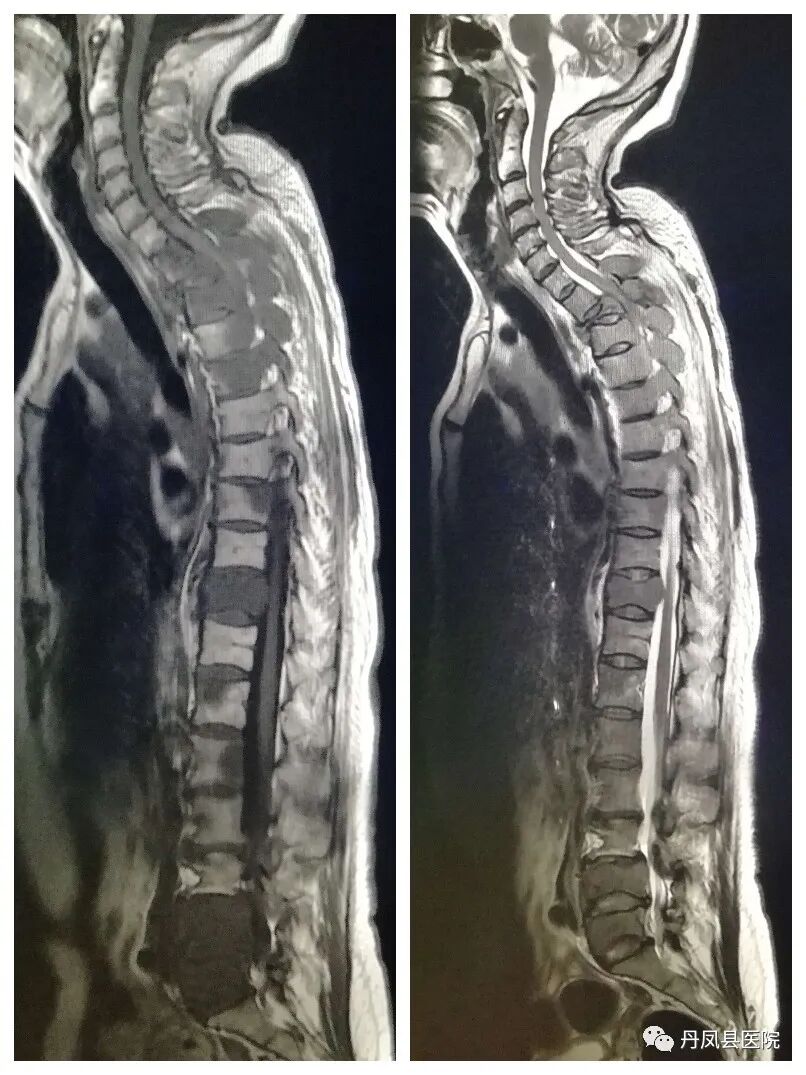

开展项目MRI磁共振设备是我县第一台检查设备,其扫描速度快、噪音低、图像分辨率高,能够进行全身各部位磁共振平扫、增强扫描及血管成像(MRA、MRV)、功能成像(DWI、DTI、SWI、MRS)、灌注成像、胰胆管水成像(MRCP)、泌尿系水成像(MRU)等检查。尤其在中枢神经系统、胆道系统、脊柱判断新旧骨折、骨转移瘤、早期股骨头缺血坏死、关节软骨损伤、韧带肌腱损伤有不可替代的优势,为临床提供更多、更丰富的影像诊断信息。磁共振的多方位、多参数、多轴倾斜断层对中枢神经系统病变的定位、定性诊断极其优越。中枢神经系统疾病的诊断中,除颅骨骨折和颅内急性出血不及CT外,在脑部肿瘤、颅内感染、脑血管病变、脑白质病变、脑发育畸形、脑退行性病变、脑室及蛛网膜下腔病变、脑挫伤、颅内亚急性血肿及脊髓的肿瘤、感染、血管性病变及外伤的诊断有明显优势。

![磁共振脊柱全场拼接.jpg]()

磁共振脊柱全长拼接